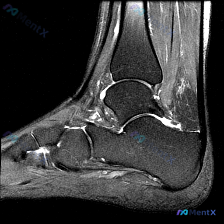

看到一份踝关节MRI的读片问题,问题问的是「图像可能有什么软骨异常相关发现」,整理了病例影像资料和分析思路分享给大家。 病例影像基础信息 这是踝关节MRI-T1加权矢状位图像,可观察范围包括胫骨远端、距骨、跟骨、舟骨及部分足底结构: - 骨皮质、骨髓信号符合T1加权正常表现,距骨跟骨骨小梁结构可见...

今天整理了一份踝关节MRI的读片分析,核心问题是影像发现「软组织积液」该怎么判断,分享出来大家一起讨论。 病例影像基础信息 这是一份踝关节轴位T2加权MRI(T2WI)的读片报告,核心信息整理如下: 1. 骨骼结构:胫骨远端、距骨骨髓信号正常,无骨髓水肿、骨质破坏,皮质完整,未见骨折线 2. 关节结...